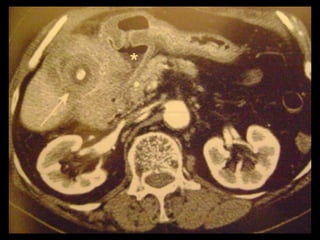

Colecistite Xantogranulomatosa

Na TC:

Os cálculos biliares e o espessamento irregular

semelhante a uma massa da parede da VB são as

anormalidades mais comuns.

Vários estudos relataram que os nódulos

hipoatenuantes intramurais vistos na TC

representam uma lesão xantogranulomatosa, um

abscesso ou a combinação de ambos;

Realce da superfície luminal(70%) correspondia à

presença de uma camada epitelial.

O radiologista deve distinguir entre a colecistite

xantogranulomatosa e o carcinoma da vesícula

biliar

Linha de mucosa evidente

Realce da superfície luminal

Nódulos intramurais hipoatenuantes(TC) ou com

sinal alto(RM T2)